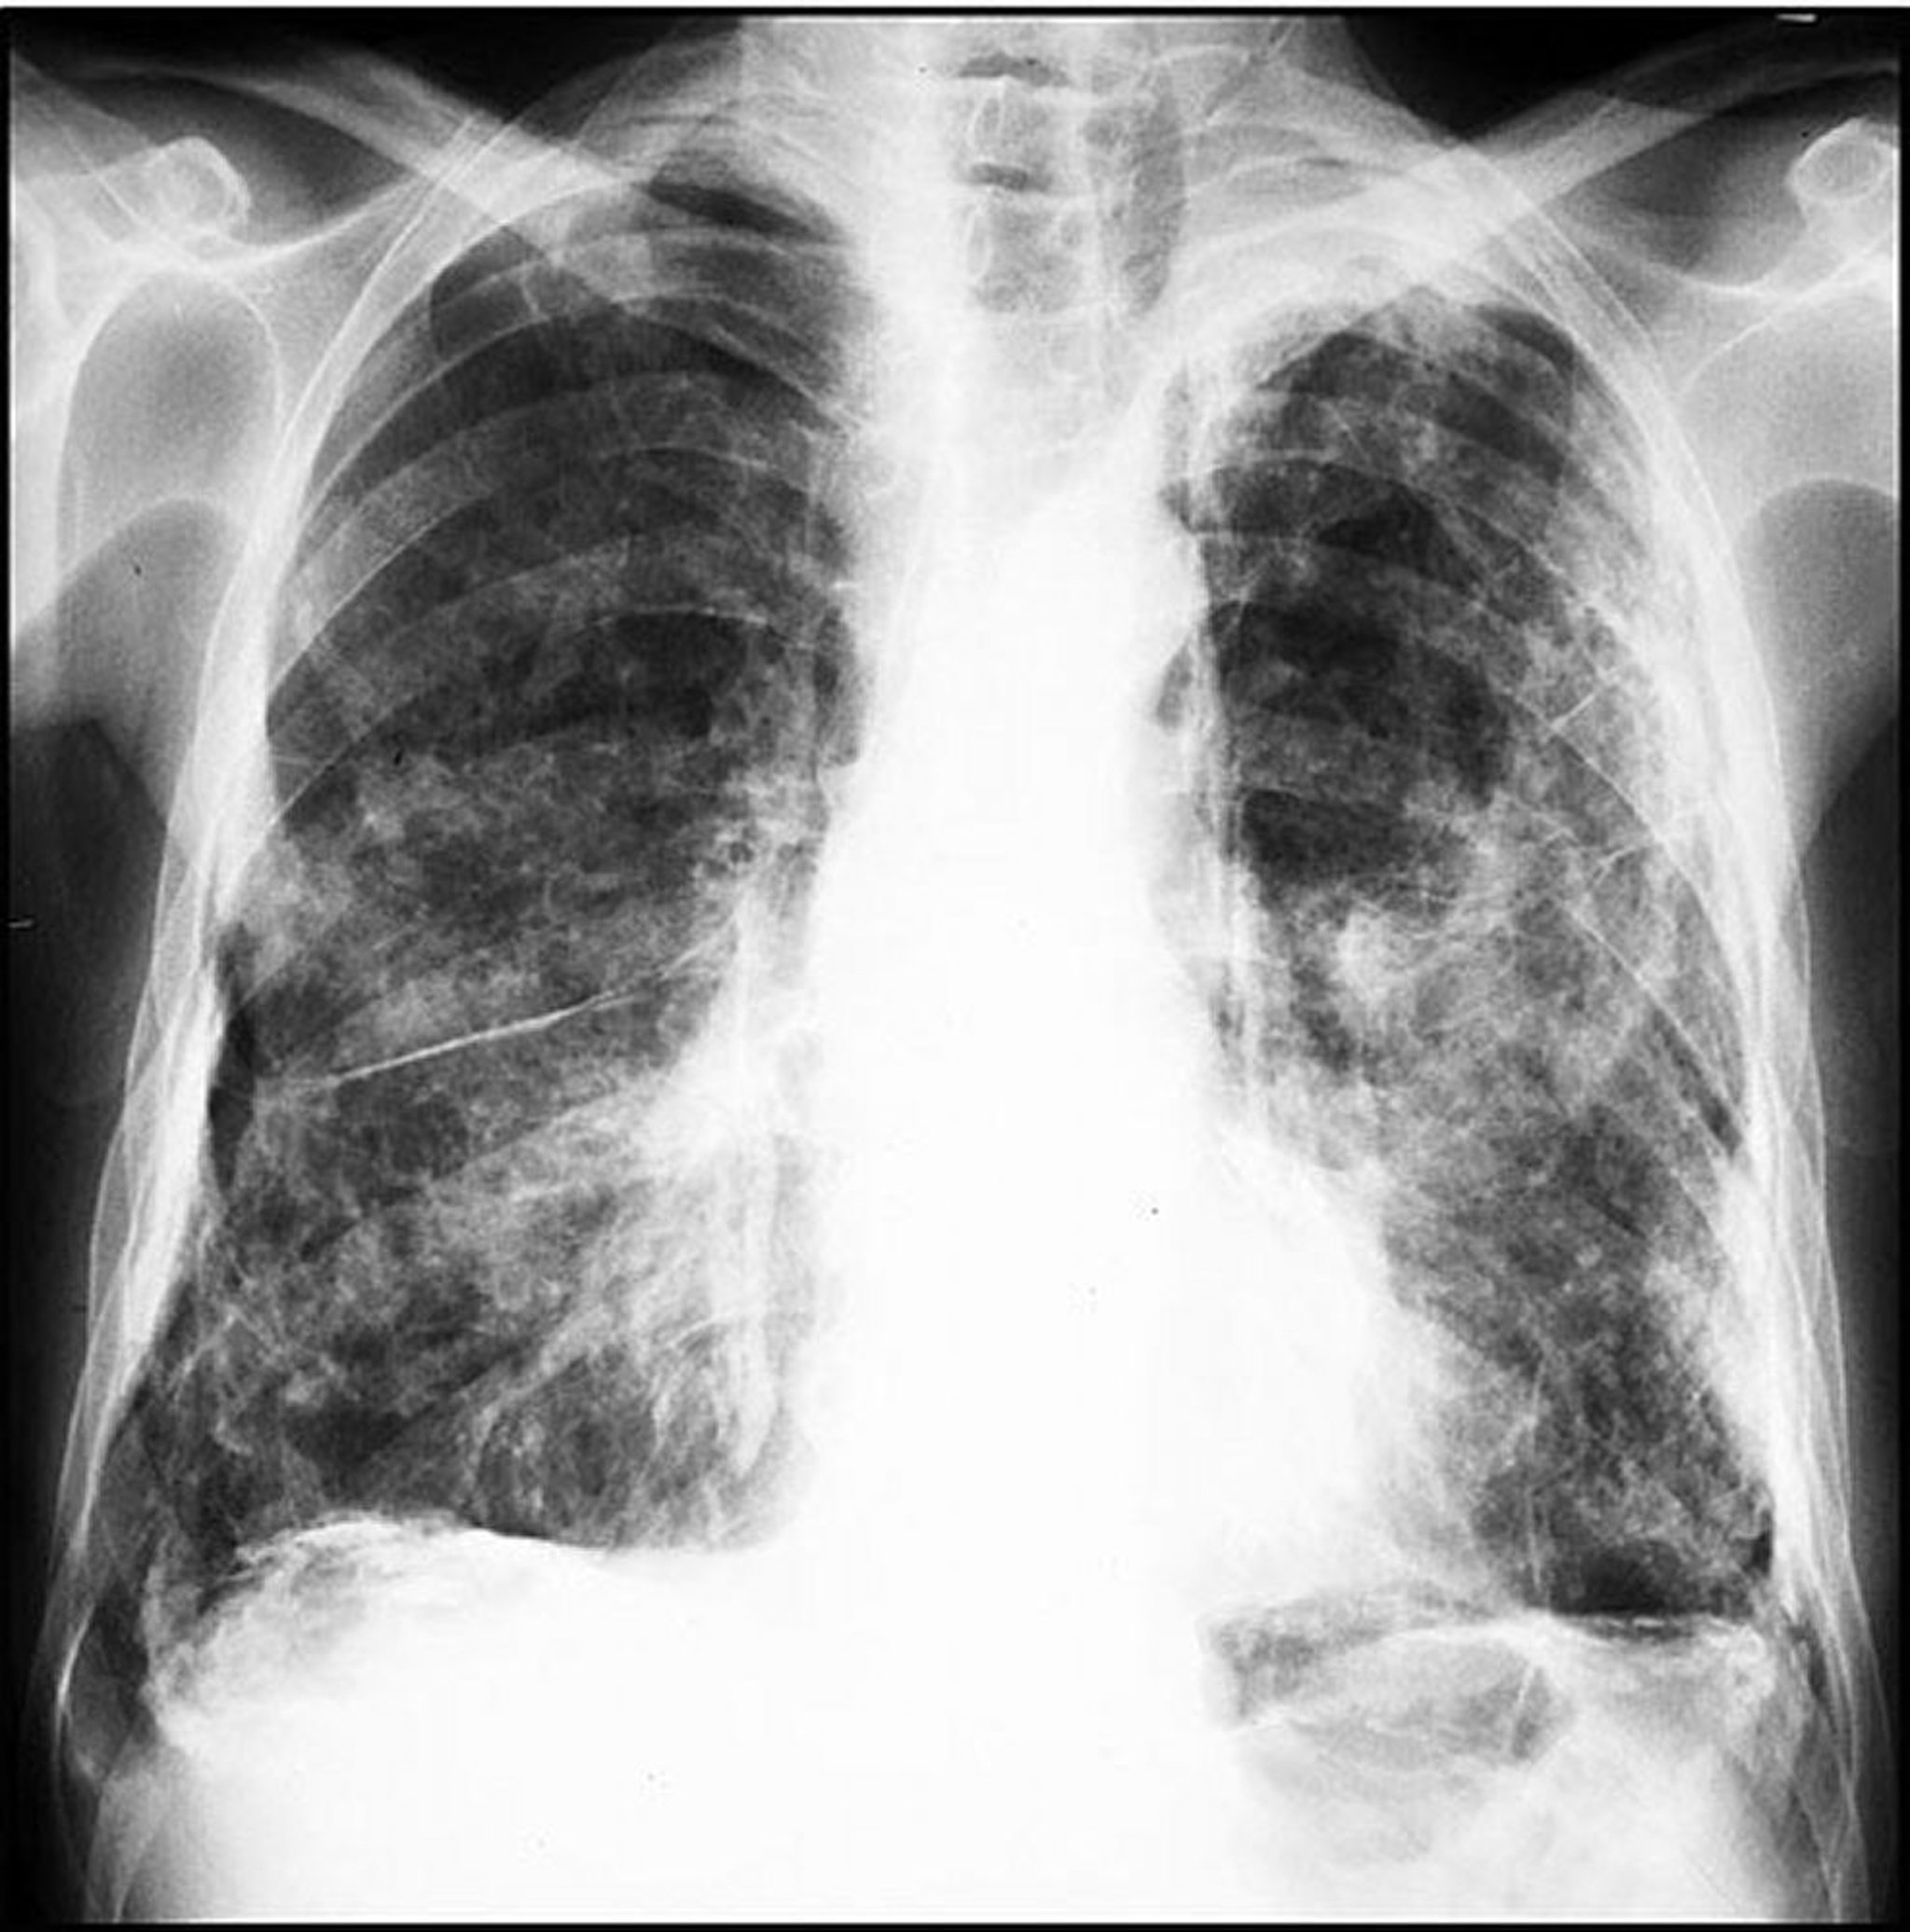

Plaques liées à l'amiante (extensives)

Image courtoisie de David W. Cugell, MD.